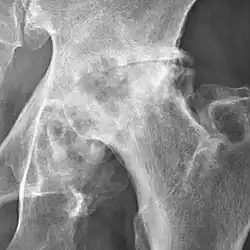

Hip joint with no signs of osteoarthritis.

The most commonly used radiographic classification system for osteoarthritis of the hip joint is the Kellgren–Lawrence system (or KL system).[6] It uses plain radiographs.